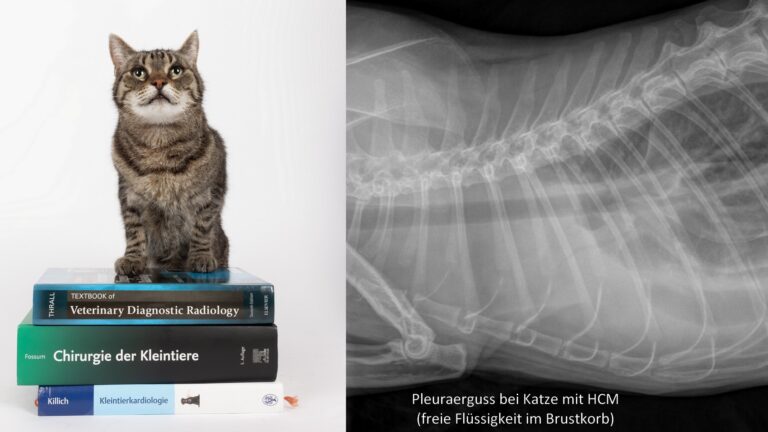

Die häufigsten erworbenen Herzerkrankungen sind Herzmuskelerkrankungen (v.a. bei der Katze) und Herzklappenerkrankungen (v.a. beim Hund). Es kann ein verdickter Herzmuskel vorliegen (Hypertrophe Kardiomyopathie, HCM der Katze) oder eine Schwäche und Ausdünnung des Herzmuskels (Dilatative Kardiomyopathie, DCM, vor allem bei großen Hunderassen). Die degenerative Herzklappenerkrankung führt zur Klappenundichtigkeit (= Insuffizienz). Der häufigste Befund in der Praxis ist die Mitralklappeninsuffizienz.

Um eine Herzerkrankung korrekt zu diagnostizieren reicht es nicht, ein Tier abzuhören. Das Vorliegen eines Herzgeräuschs oder einer Rhythmus-Veränderung ist nicht beweisend für eine Herzerkrankung. Beim Verdacht auf eine Herzerkrankung müssen mindestens ein Herzultraschall und ein EKG durchgeführt werden. Beides ist am wachen Patienten möglich und für das Tier nicht belastend. Nur mithilfe dieser Untersuchungsmethoden kann eine klare Diagnose gestellt werden. Diese ist nötig, um eine zu planen. Es gibt weitreichende Therapieoptionen, die von Medikamenten über Fütterungs- und Management-Maßnahmen bis hin zu Operationen reichen. Wichtig ist außerdem, Begleiterkrankungen oder andere Grundursachen zu finden.